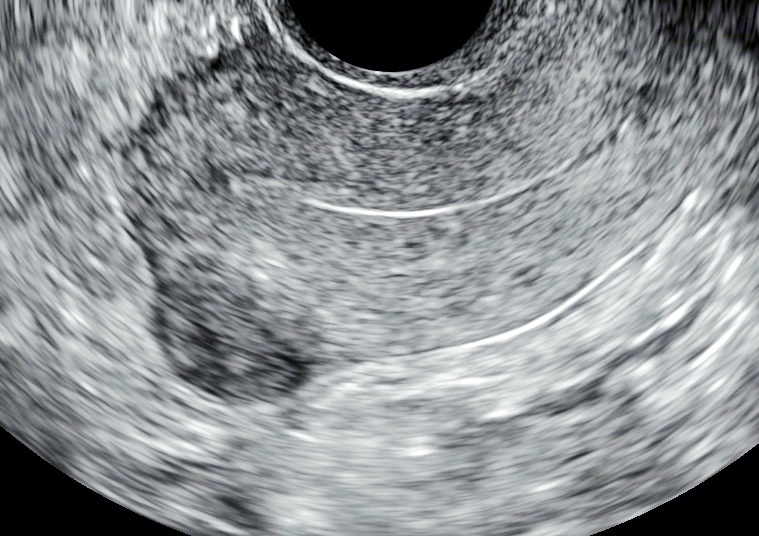

УЗ-признаки миомы матки малых размеров.